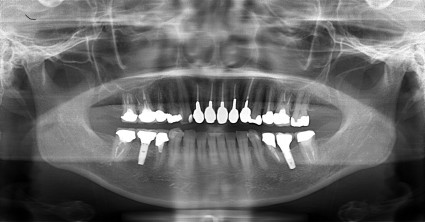

患者様は 右下の歯のない部分と かみ合わせの不調和を感じられ当院に受診されました。

上下のかみ合わせのバランスも一緒に整えた

インプラント治療と かみ合わせのバランスを整えることを 同時に 施術した患者さまです。

治療後は 右の笑顔が上手にできるようになりました!

仕事で大勢のみなさんの前でしゃべることが多いようで非常に満足されて治療を終えられ

今は定期的にメンテナンスにおいでいただいております。